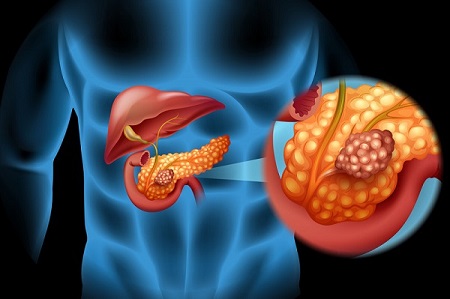

این 6 نشانه سرطان لوزالمعده را نادیده نگیرید

سرطان لوزالمعده یک بیماری بسیار تهاجمی است، و احتمال گسترش آن به اندام های دیگر بدن انسان یا متاستاز زیاد است.